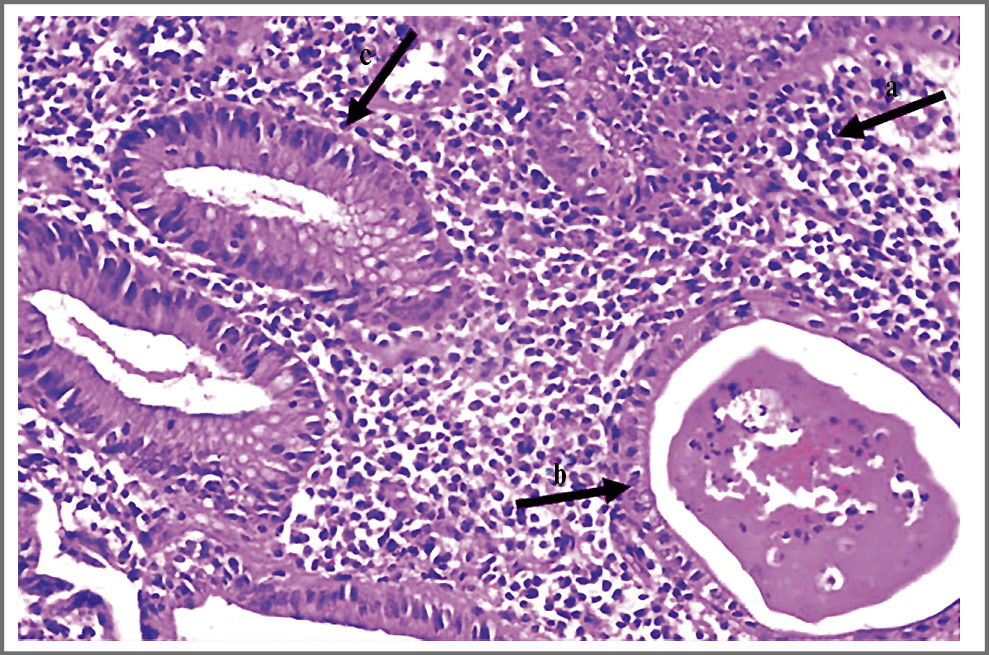

Анализы крови: Нb – 108 г/л, эритроциты – 4,21×1012/л, гематокрит – 33,3%, MCV – 79 фл, MCH – 25,7 пг, тромбоциты – 478×109/л, лейкоциты – 15,1×109/л, нейтрофилы – 75,7%, лимфоциты – 10,6%, моноциты – 11,9%, эозинофилы – 1,0%, базофилы – 0,8%; СРБ – 172,83 мг/л, фибриноген – 7,56 г/л, РСТ – 0,5 нг/мл, общий белок – 43,1 г/л. Посев содержимого абсцесса носовой перегородки: рост Staphylococcuc epidermidis в низком титре (по-видимому, контаминация материала при заборе пробы). Рентгенография придаточных пазух носа: лобные/гайморовы пазухи носа прозрачны. Видеоколоноскопия: слизистая оболочка в доступных осмотру отделах гиперемирована, отечна, с зернистой поверхностью, множественными эрозиями, покрытыми фибрином, вязкой слизью. Отмечается контактная кровоточивость. Выполнена биопсия. Заключение: эндоскопическая картина ЯК средней степени активности. Гистологическое заключение (рис. 4, 5): фрагменты слизистой оболочки толстой кишки с очаговым некрозом поверхностного эпителия и инфильтрацией соединительнотканной стромы до собственной пластинки лимфоцитами, плазматическими клетками в умеренном количестве, местами с участками формирования небольших лимфоидных фолликулов.

Рис. 4. Фрагмент слизистой оболочки толстой кишки с очаговым некрозом поверхностного эпителия (a). Край язвенного дефекта. Воспалительный инфильтрат проникает через мышечную пластинку в подслизистый слой, с участками формирования лимфоидных фолликулов без светлых центров (b). Формирование воспалительного полипа (c). Окраска гематоксилином и эозином ×200.